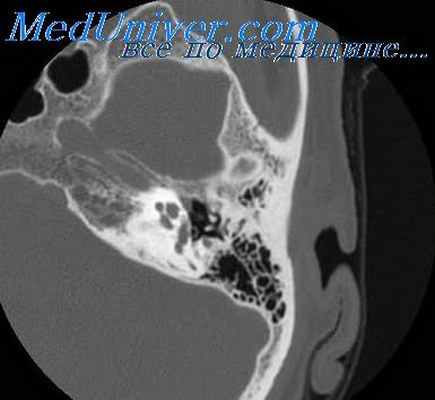

КТ височных костей в аксиальной и фронтальной проекциях по программе костной реконструкции с толщиной среза 0,6 мм и с денситометрией, которая выполнена в 13 случаях, выявила морфологические изменения, соответствующие I—III степени облитерации по классификации J. Nadol и M. Mckenna [20]. При несоблюдении параметров выполнения КТ и некачественном ее описании в одном случае отосклероз не был верифицирован. В 4 случаях (3 больных) на томограммах выявлялся очаг отосклероза в области впередиоконной щели в сочетании с достаточно равномерным утолщением и уплотнением основания стремени (рис. 1). Рис. 1. КТ правой височной кости. Аксиальная проекция. Небольшой очаг отоспонгиоза в области впередиоконной щели (стрелка). Равномерное утолщение подножной пластинки стремени на всем протяжении (стрелки). В 6 наблюдениях (5 больных) определялись очаги отоспонгиоза по краям ниши окна преддверия, значительно суживающие ее. Толщина центральных отделов подножной пластинки при этом была не изменена (рис. 2). Рис. 2. КТ левой височной кости. Аксиальная проекция. Крупные очаги отоспонгиоза низкой плотности по краям ниши окна преддверия, распространяющиеся на подножную пластинку и ножки стремени (стрелки). Центральные отделы подножной пластинки стремени не изменены. В 7 случаях (6 больных) отмечались отоочаги по краям ниши окна преддверия в сочетании с выраженным равномерным утолщением и уплотнением основания стремени (рис. 3). Рис. 3. КТ левой височной кости. Аксиальная проекция. Очаги отосклероза высокой плотности в области впереди- и позадиоконной щели. Значительное утолщение и уплотнение подножной пластинки стремени на всем протяжении (стрелка). Наиболее наглядно на КТ височных костей облитерация окна преддверия визуализировалась в коронарной проекции (рис. 4). Рис. 4. КТ правой височной кости. Коронарная проекция. Облитерация ниши окна преддверия за счет смыкания плотных отоочагов, расположенных на промонториуме и в области канала лицевого нерва (стрелка). При этом фенестральная локализация очагов отосклероза выявлена в 7 случаях, смешанная — в 6, что не соответствует формам отосклероза по данным ТПА (тимпанальная — у 4 и смешанная — у 13). Консервативное инактивирующее лечение перед операцией вследствие выраженной деминерализации очагов отосклероза (плотность

Особого внимания заслуживает рентгенологический метод диагностики отосклероза — выявляются мельчайшие детали морфологического строения височной кости и обнаруживаются характерные изменения в области окон преддверия и улитки, полукружных каналов и внутреннего слухового прохода.

КТ: На КТ височных костей обнаруживаются очаги новообразованной кости вокруг овального, круглого окна и/или отосклеротические очаги в костной капсуле лабиринта – «симптом ореола».